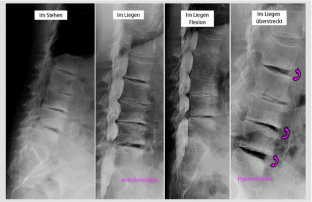

Abb. 1